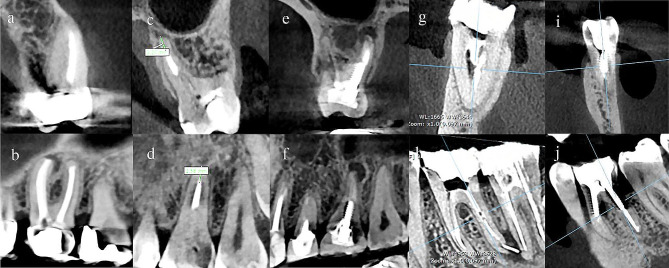

The data from independent variables recorded by the examiner were as follows: tooth number, gender, jaw type, the status of missed canals and their quantity, obturation material length, type of restoration, presence of a separated instrument, presence of a post/screw in the canals, presence of perforation (Fig. 1). Length of obturation was classified as appropriate if the ending was at a distance of 0–2 mm from the apex, underfilled when it was shorter than 2 mm from the apex, and overfilled if the material extruded the apex [3].

Fig. 1.

(a, c, e, g, and i): Coronal view of the teeth, (b, d, f, h, and j): Sagittal view of the teeth. (a, b): Upper left first molar with missed MB2 canal, PL, and a PFM crown; (c, d): Upper left first molar with a underfilled palatal canal; (e, f): Upper right first molar with a screw in the palatal canal, PL, and composite restoration; (g, h): Lower right first molar with separated instrument in the distal canal and PL; (i, j); Lower left first molar with furcal lesion (excluded from the study)